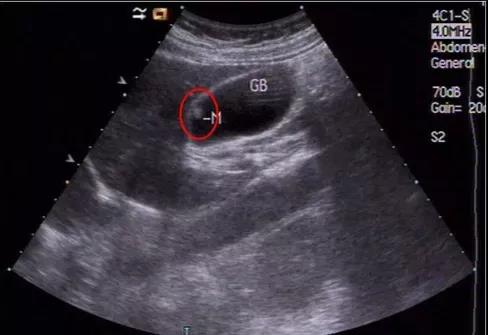

(▲膽囊假性息肉)